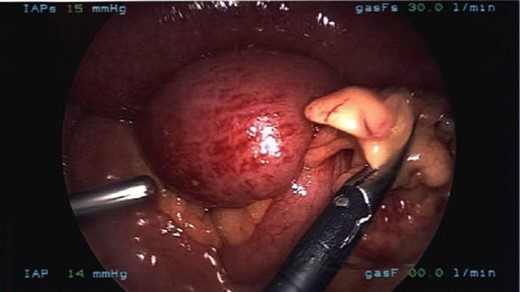

Laparoscopy showed an obstruction of the small bowel caused by a bifid omentum that wrapped around the distal jejunum, adhering to its walls (Fig. 6). A clear transition point was appreciated. The band of omentum was lysed and the proximal bowel decompressed. The patient remained in hospital and had an uncomplicated postoperative recovery.

Laparoscopic visualization of the transition point of the obstruction in the distal jejunum caused by a band of omentum.